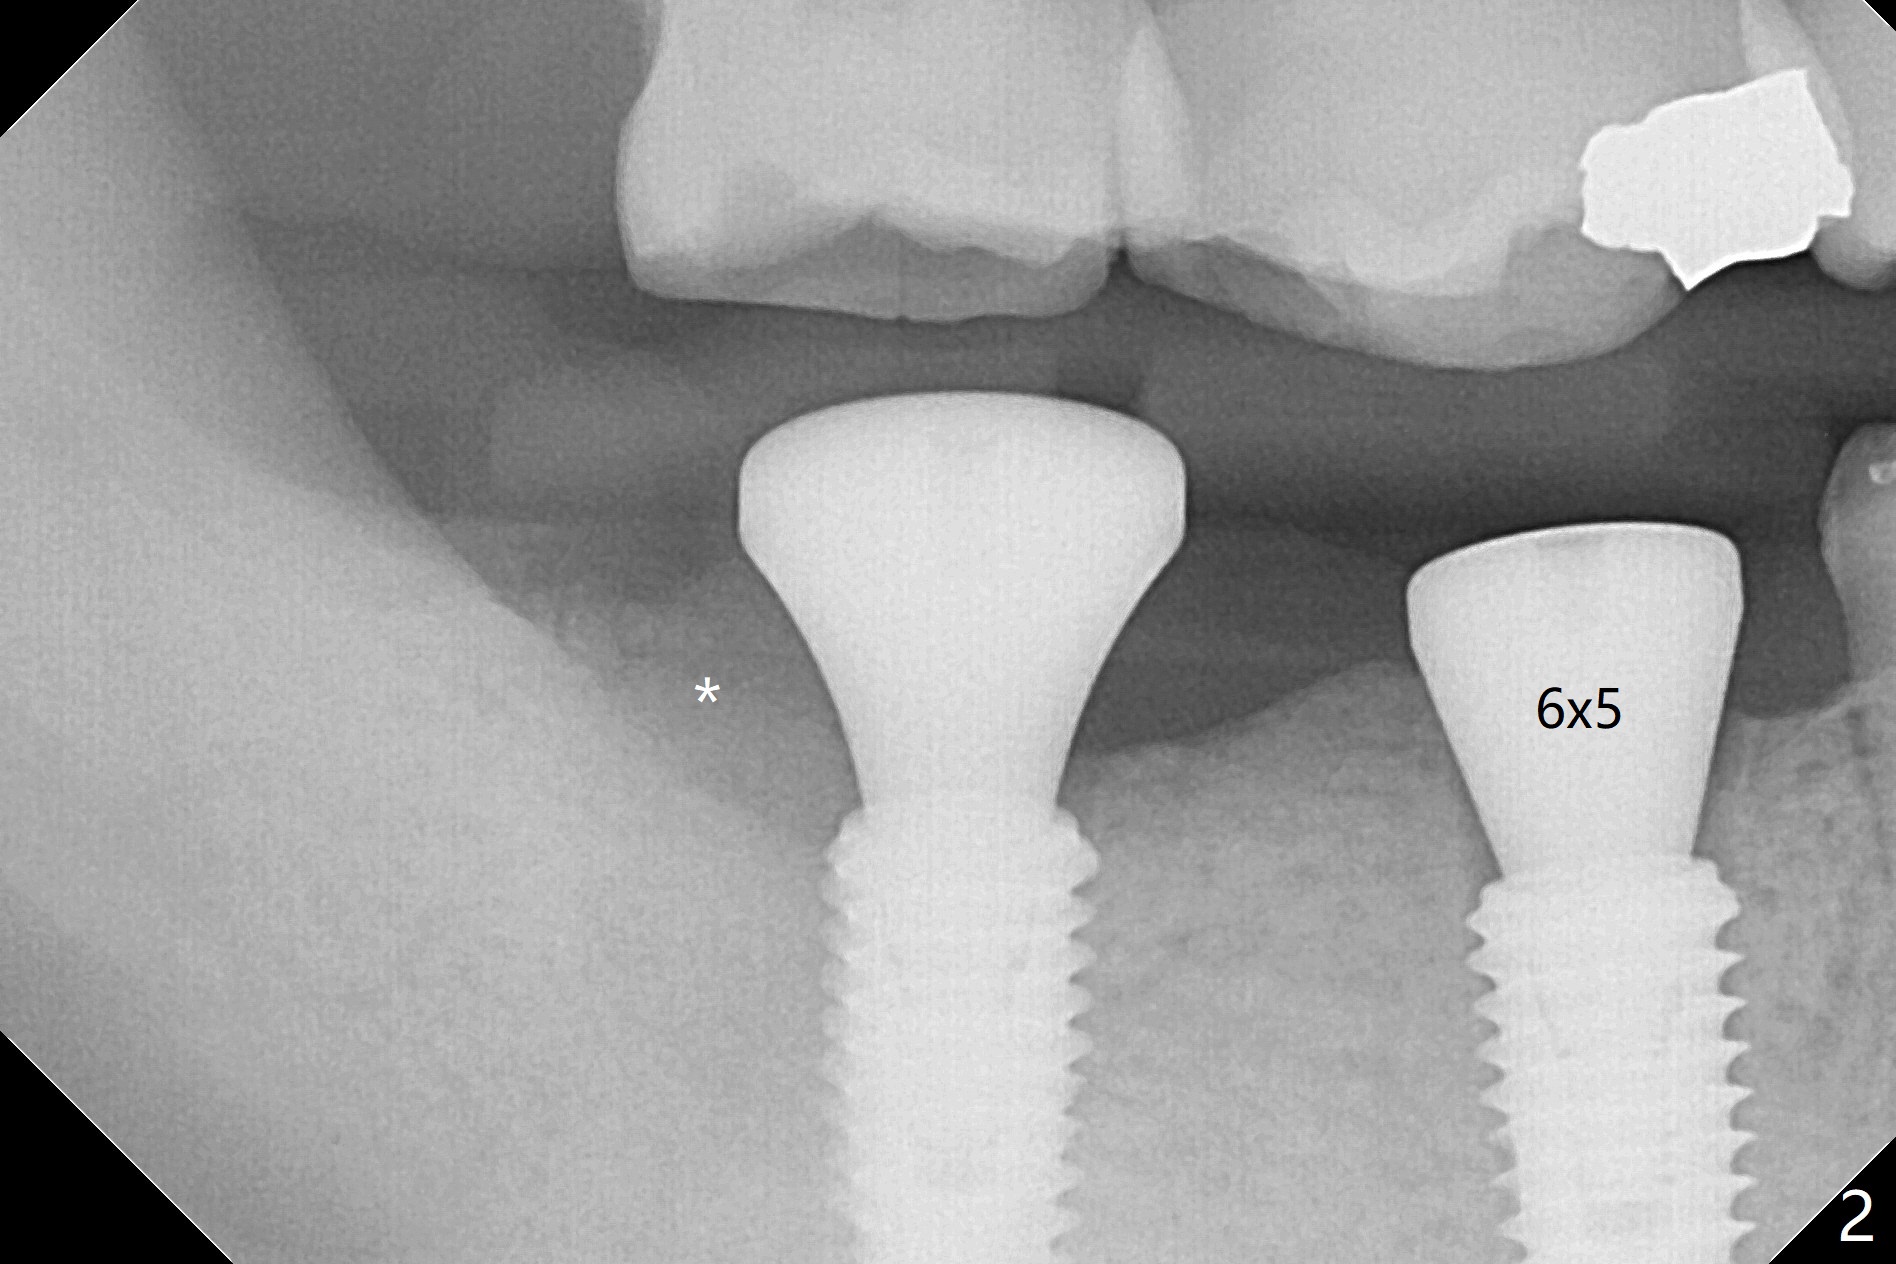

The bone at #30 and 31 is so hard that plenty of bone shaving is saved as bone graft to be placed in the socket of #31 post implantation (Fig.1,2 * (blue dashed line: #31 socket)). The guide is long and stable, allowing osteotomy without use of an anchor pin. Since the vertical space is limited, no provisional is fabricated. The bone graft is kept in place with collagen plug on the top and suturing. No provisional is fabricated because of limited vertical space (Fig.2). It appears necessary to intrude #2 and 3, which seems difficult since the patient is a bruxer (hard bone). The implants are placed as planned because of metal tubes (Fig.3). The patient develops postop pain, which is relieved by taking 800-1000 mg Ibuprofen every night. Exam shows mild percussion at the tooth #29 with gutta percha extrusion and periapical radiolucency (Fig.1,3). An endodontist refuses #29 RCT retreatment. What should be done?